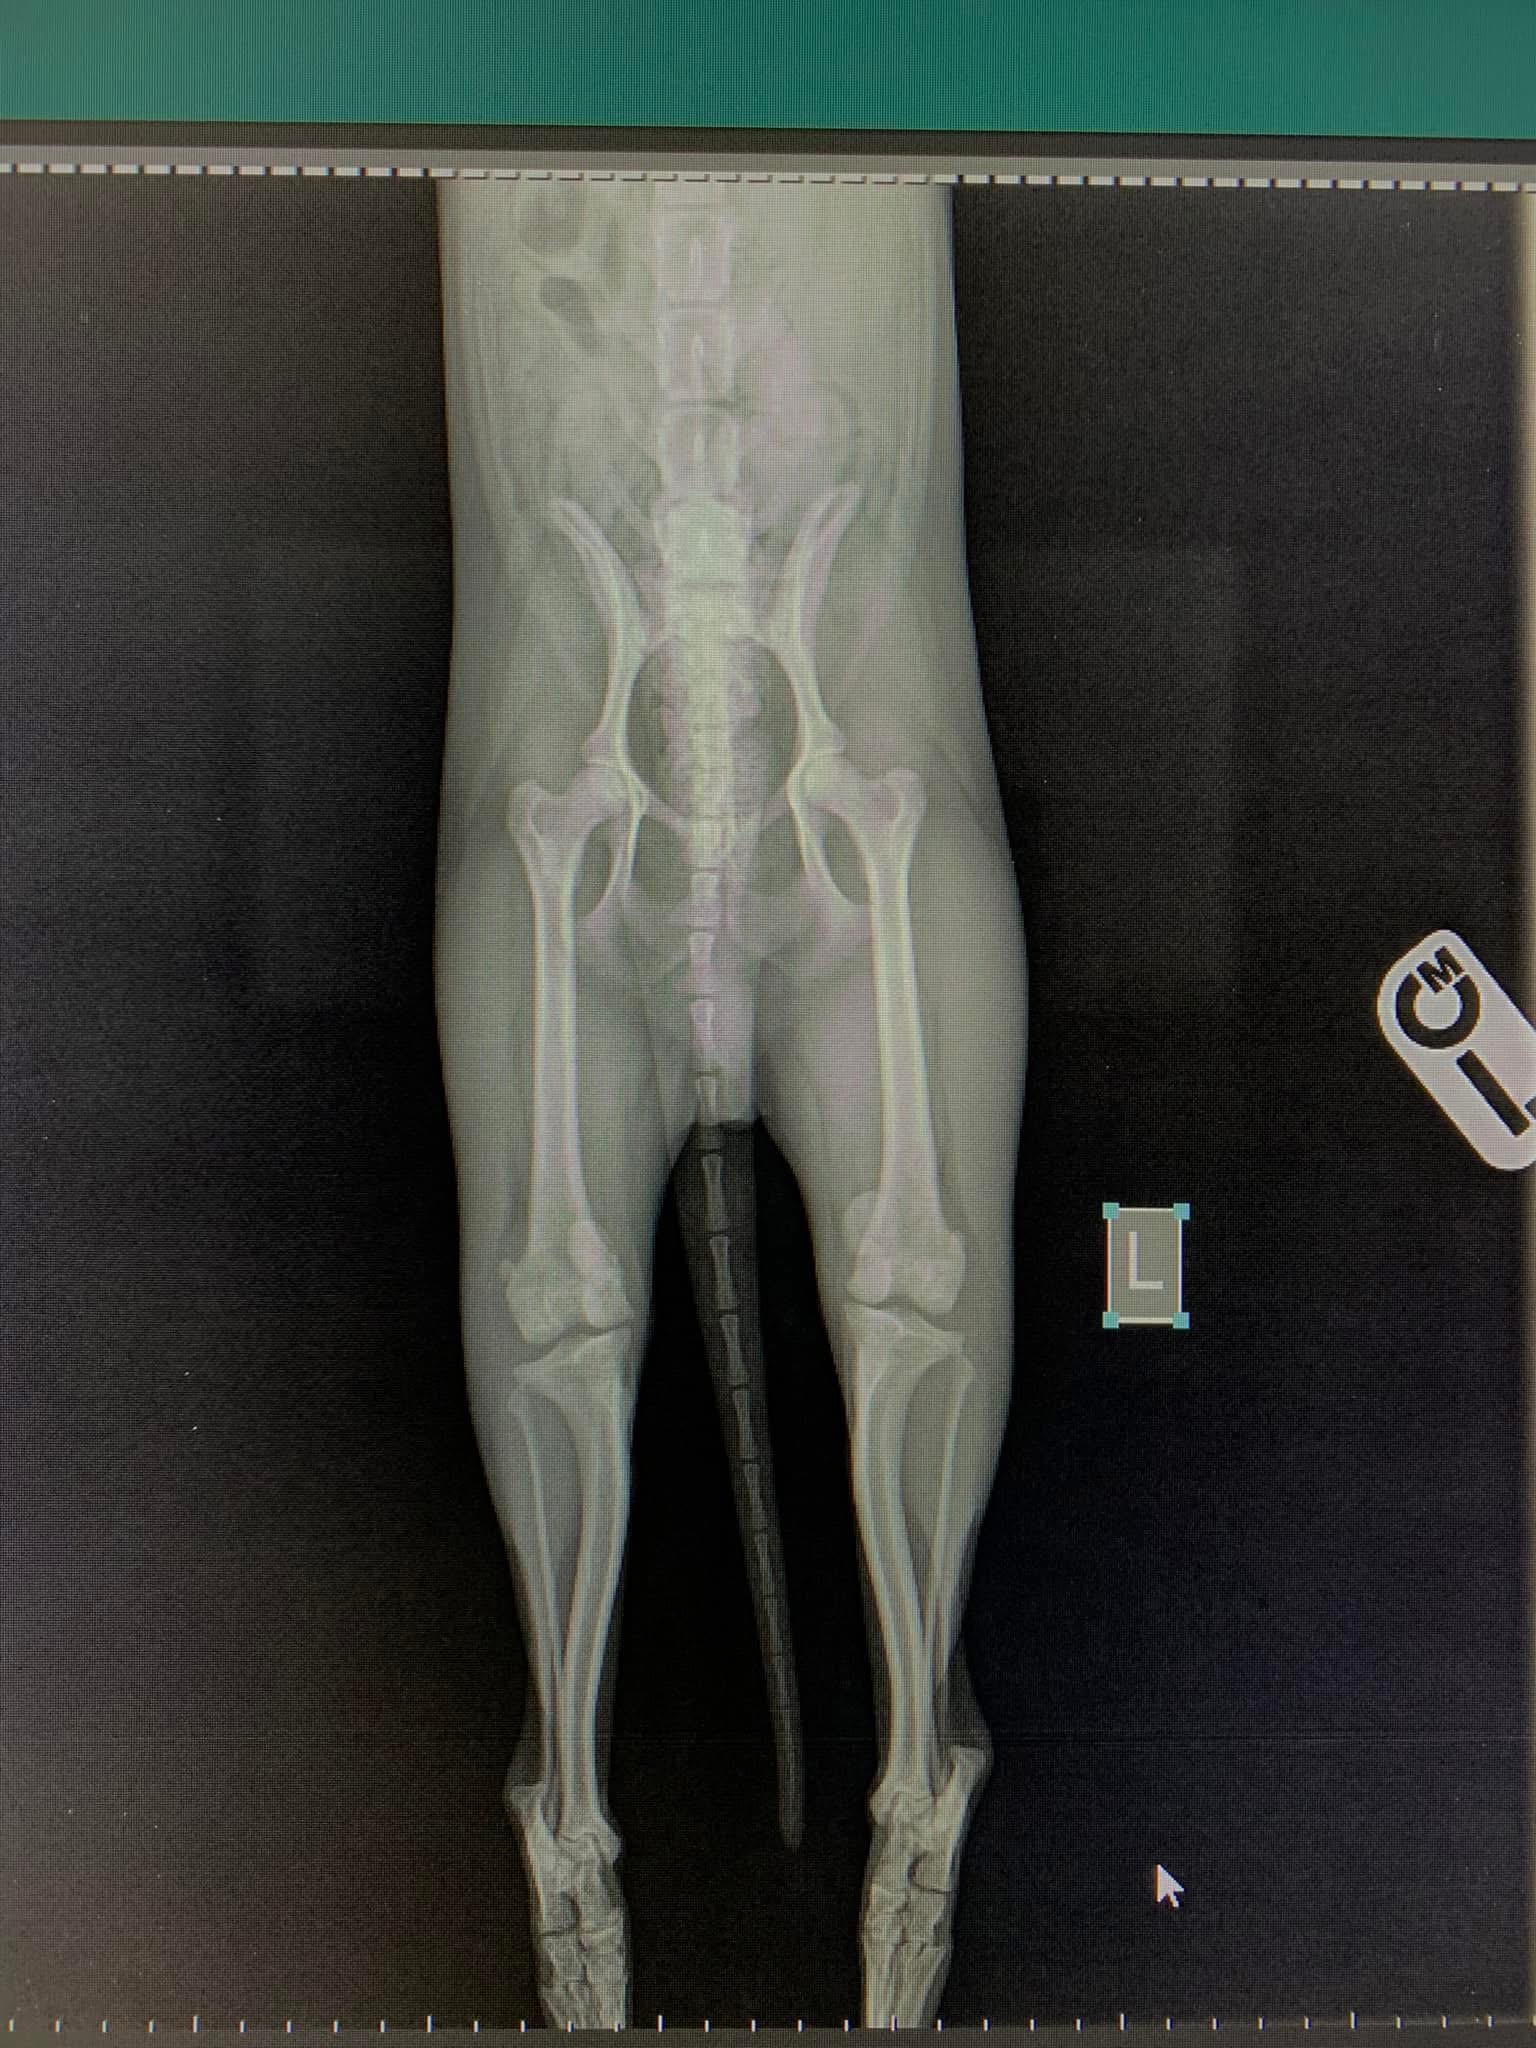

Psi i mačke su aktivne životinje sklone ortopedskim povredama, a najčešći uzroci su saobraćajne nesreće, padovi, udarci.

Genetika i degenerativni procesi često igraju ključne uloge u razvoju različitih problema sa kostima, zglobovima, ligamentima i hrskavicom, što može biti prisutno od rođenja ili se razvija tokom rasta životinje. Ortopedske povrede ozbiljno utiču na kvalitetu života ljubimaca, ali uz pravovremenu dijagnozu i terapiju se mogu uspješno oporaviti.

- Liječenje luksacije patele(Luxatio Patellae) Trohleoplastika i TTT(eng. Tibial Tuberosity Transposition)

- Liječenje rupture prednjeg križnog ligamenta koljena TPLO (eng. Tibial Plateau Leveling Osteotomy)